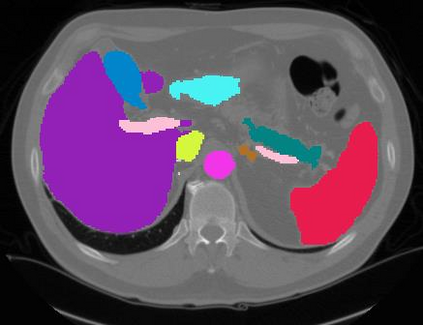

Vision transformers, with their ability to more efficiently model long-range context, have demonstrated impressive accuracy gains in several computer vision and medical image analysis tasks including segmentation. However, such methods need large labeled datasets for training, which is hard to obtain for medical image analysis. Self-supervised learning (SSL) has demonstrated success in medical image segmentation using convolutional networks. In this work, we developed a \underline{s}elf-distillation learning with \underline{m}asked \underline{i}mage modeling method to perform SSL for vision \underline{t}ransformers (SMIT) applied to 3D multi-organ segmentation from CT and MRI. Our contribution is a dense pixel-wise regression within masked patches called masked image prediction, which we combined with masked patch token distillation as pretext task to pre-train vision transformers. We show our approach is more accurate and requires fewer fine tuning datasets than other pretext tasks. Unlike prior medical image methods, which typically used image sets arising from disease sites and imaging modalities corresponding to the target tasks, we used 3,643 CT scans (602,708 images) arising from head and neck, lung, and kidney cancers as well as COVID-19 for pre-training and applied it to abdominal organs segmentation from MRI pancreatic cancer patients as well as publicly available 13 different abdominal organs segmentation from CT. Our method showed clear accuracy improvement (average DSC of 0.875 from MRI and 0.878 from CT) with reduced requirement for fine-tuning datasets over commonly used pretext tasks. Extensive comparisons against multiple current SSL methods were done. Code will be made available upon acceptance for publication.